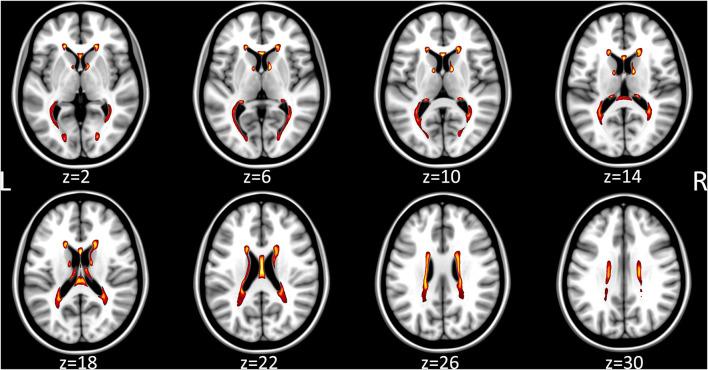

Diffusion tensor imaging was obtained in 100 MS patients and 24 healthy matched controls to compare seed-based tract characteristics descending from the superior parietal lobule [Brodman area 7A (BA7A)], atlas-based tract characteristics from the superior longitudinal fasciculus (SLF), and control tract characteristics from the corticospinal tract (CST) and their respective association with ability on the SDMT.

Patients had decreased performance on the SDMT and decreased white matter volume (each < 0.05). The mean fractional anisotropy (FA) for the BA7A tract and CST ( < 0.05), but not the SLF, differed between MS patients and controls. Furthermore, only the FA of the SLF was positively associated with SDMT performance even after exclusion of the lesions within the tract ( = 0.25, < 0.05). However, only disease disability and total white matter volume were associated with information processing speed in a linear regression model.